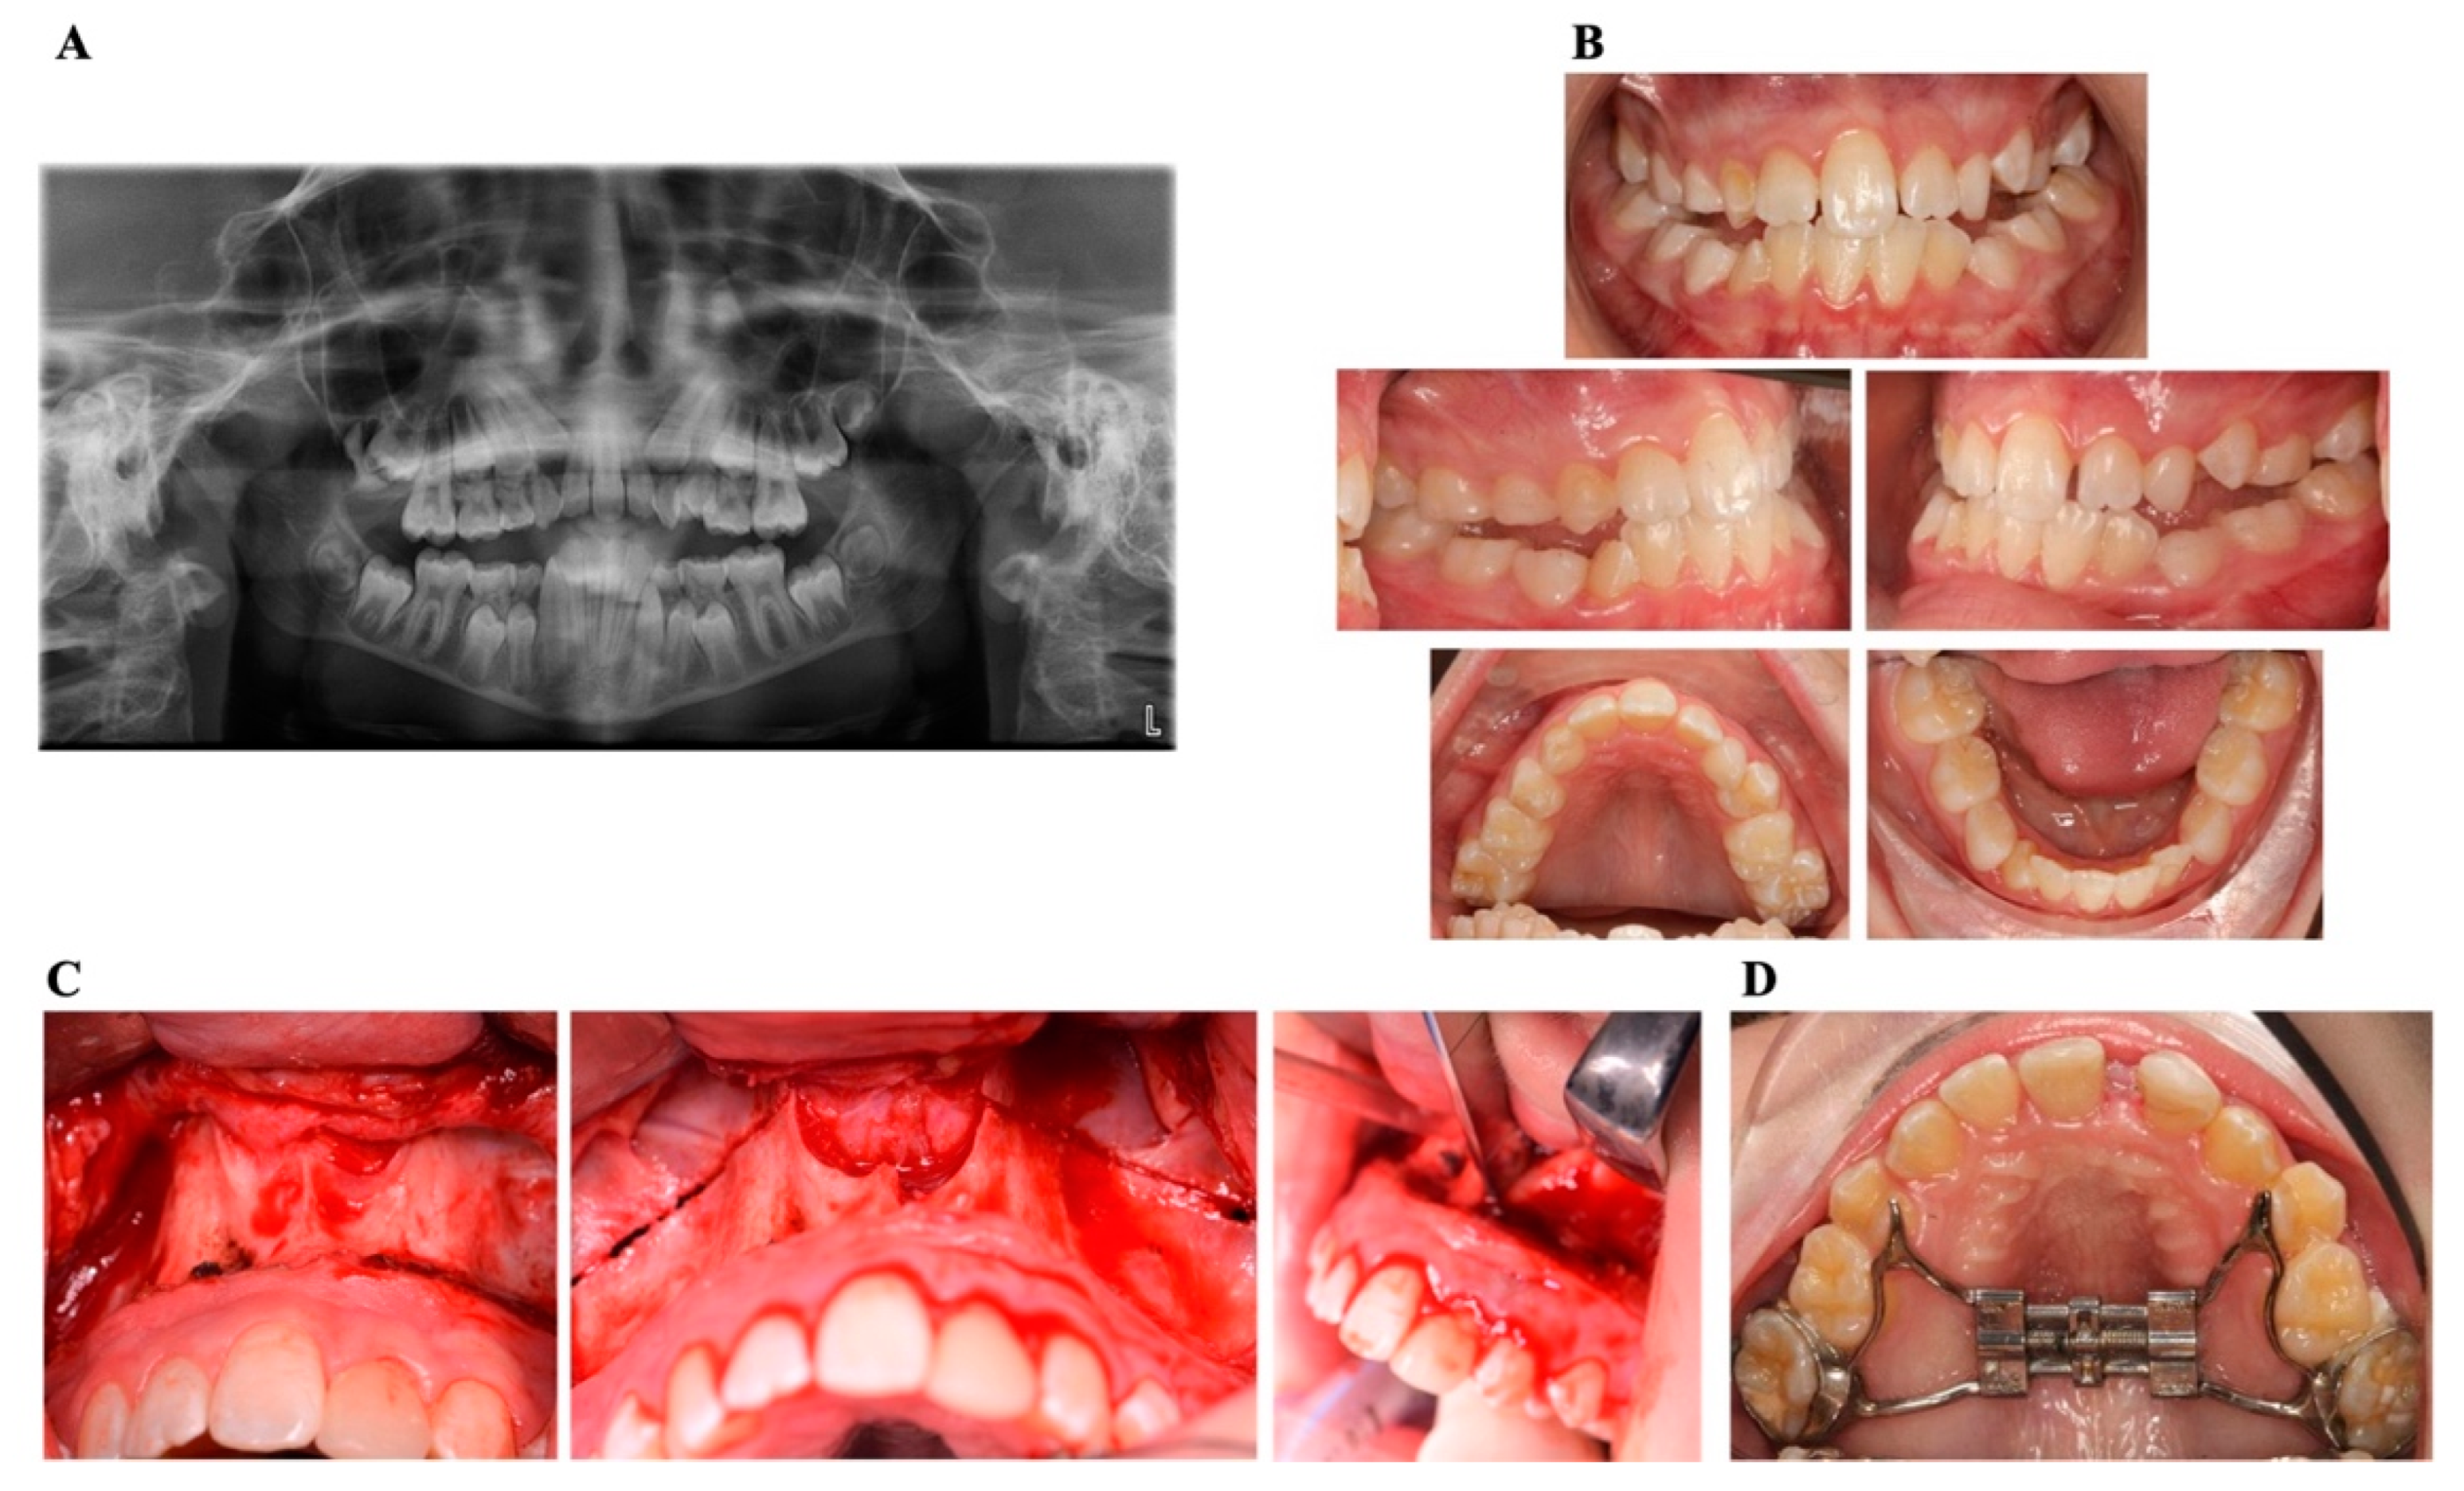

| 1 | 11 years | Piriform aperture stenosis, nasal stenosis, single central incisor | Nasal obstruction, failed orthodontic expansion, skeletal discrepancy | Quad-Helix expansion (unsuccessful) | Planned SARPE with paramedian osteotomy | Follow-ups |

| 2 | Patient history spans from birth to 11 years old | Upper airway obstruction, adrenal insufficiency, progressive hearing loss | Cyanosis at birth, respiratory distress, sleep-related breathing difficulties | Neonatal surgery (incomplete correction), hearing aid placement | Conservative management, ENT and audiology follow-up; Late intervention: planned surgical airway expansion | Underwent SARPE at age 11; current follow-ups at age 14 |